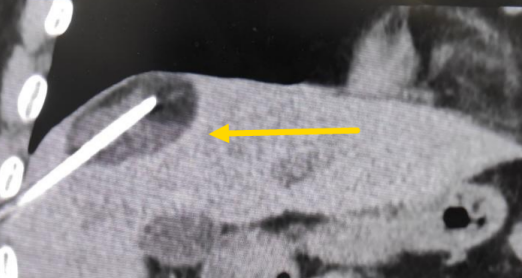

影像診療科陳寶瑩主任團隊評估后指出,較大的腫瘤位于肝頂部緊貼膈肌,如果繼續(xù)發(fā)展,腫瘤很可能突破肝包膜侵犯到膈肌,建議及時干預(yù)。病變緊臨膈肌,如果要完全消融,膈肌損傷的可能性就比較大,與其他局部治療方式比較,冷凍消融對周圍臟器、血管及神經(jīng)損傷的可能性較小、安全性更高、患者疼痛感較輕,建議通過CT精準(zhǔn)引導(dǎo)下經(jīng)皮微創(chuàng)冷凍消融治療。

這個患者病變位置刁鉆,穿刺難度大,冷凍消融的難點在于既要不損傷膈肌和肺組織,同時又要盡最大可能完全消融腫瘤。術(shù)前陳寶瑩主任、李鐵柱教授、兀云飛醫(yī)生詳細設(shè)計進針路徑、布針計劃,術(shù)中微創(chuàng)團隊協(xié)調(diào)配合,李鐵柱教授仔細操作,精準(zhǔn)到位,順利完成兩個病變的布針,遂啟動治療,先快速降溫到-150多度,再升溫至15?,經(jīng)過兩個循環(huán)反復(fù),即刻觀察到病變完全被冰球覆蓋,同時周圍臟器無損傷,術(shù)中患者幾乎沒有疼痛,還和醫(yī)生聊起了天。